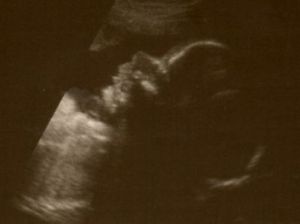

(Off topic: Seriously, doesn’t this kid have the cutest nose ever?)